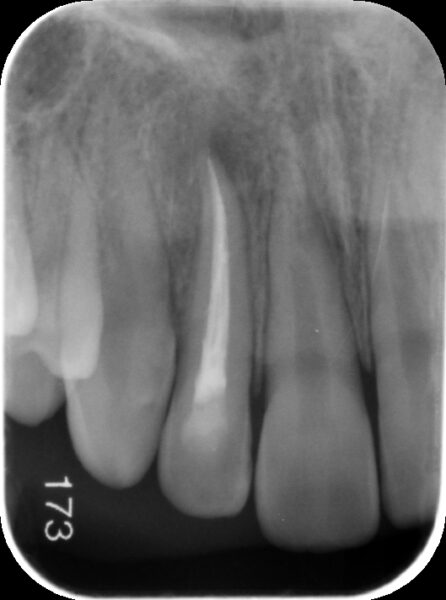

【経過観察時(術後3か月後)レントゲン】

術後3か月後のレントゲンでは黒くなっていた部分が回復してきており、骨が再生してきていることが認められました。また、根尖(根の先端)に歯が出来上がってきていることが確認されます。